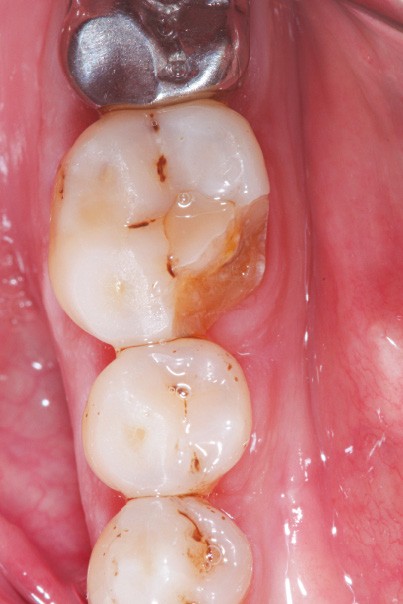

La version des dents distales peut aussi avoir des conséquences parodontales désastreuses : sur un parodonte réduit, une hypermobilité peut se développer, une poche parodontale peut aussi apparaître. Chez un patient parodontal, un « effet domino » est possible, des extractions non compensées diminueront donc le pronostic des dents restantes (fig. 7 à 9).